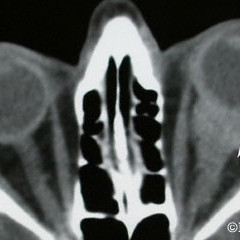

Malignant Lymphoma

Malignant Lymphoma involving the orbit, sclera and choroid (arrow) prior to radiation therapy

Magnetic resonance imaging

Magnetic resonance imaging (T2), demonstrates an nasal orbital lymphoma with subcutaneous extension (arrows).